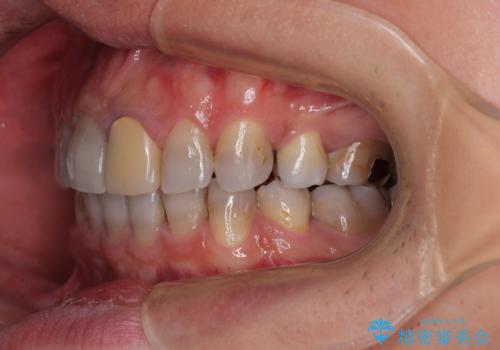

- 飛び出した前歯を気にして来院された患者様です。

口元を引っ込めるために上下左右の第一小臼歯4本を抜歯することとしました。

速やかに治療を進めたいとのことで、表側のワイヤー装置で矯正治療を行うこととしました。

特徴的な歯の色が気になっているとのことで、今後セラミッククラウンによる審美歯科治療を検討されているとのことで、矯正治療の後戻りが落ち着いたタイミングで治療を進めていく予定です。